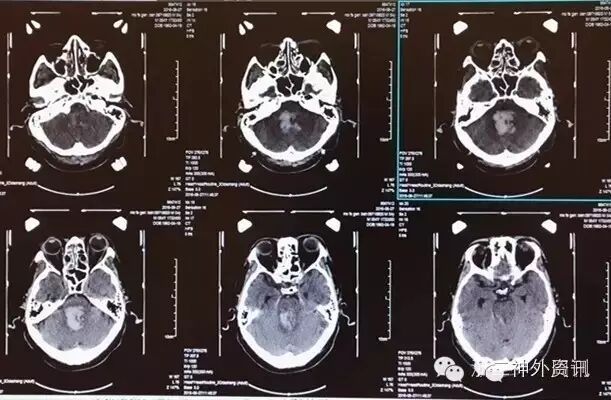

手术计划:CT三维图像评估血肿长轴,入颅点选择右枕下中线旁,靶点距离长轴最远端10mm(图3)。

图3. 立体定向手术计划。